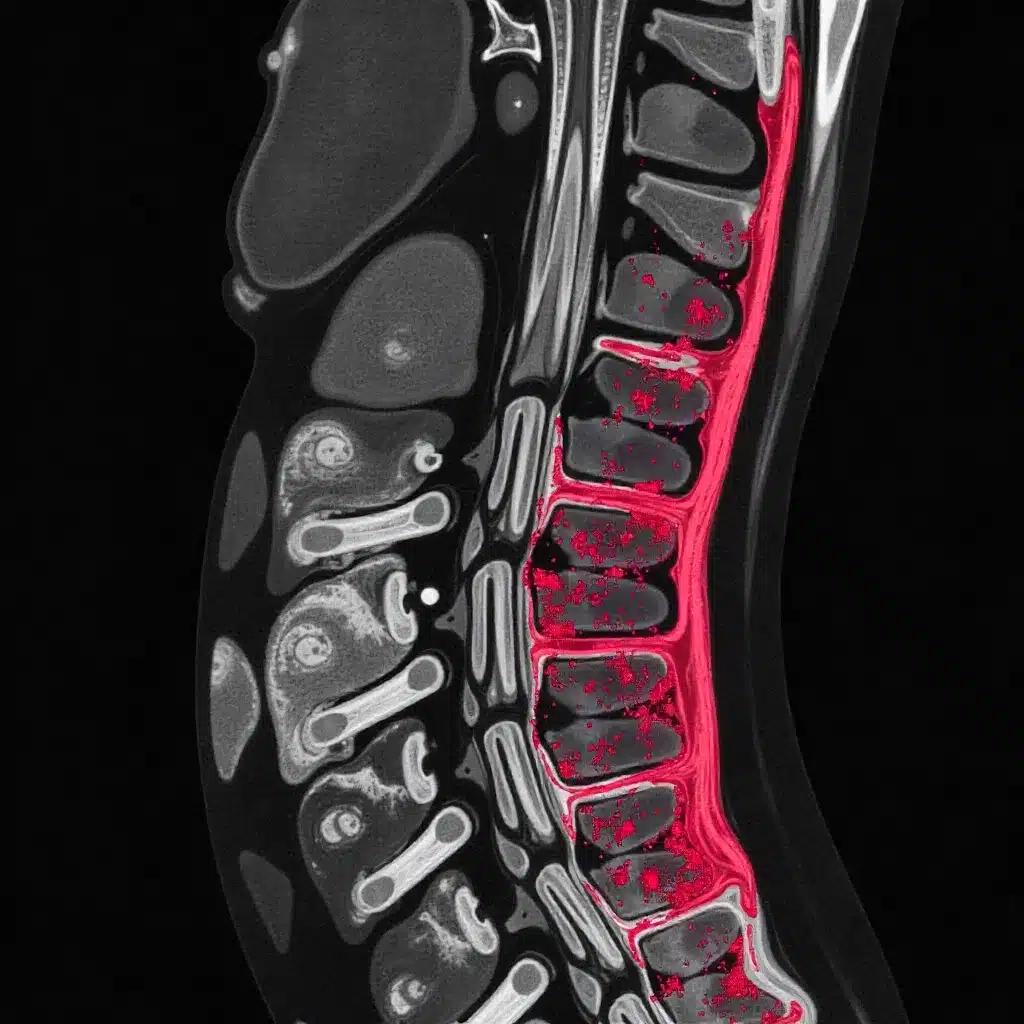

Advanced Imaging of Bone Marrow in Vertebrae

Advanced imaging has changed how we look at bone marrow in vertebrae. It gives us new insights into diseases. This helps doctors diagnose and track conditions better, leading to better care for patients.

MRI Patterns in Infiltrative Disorders

Magnetic Resonance Imaging (MRI) is key in checking bone marrow. It shows the marrow’s details and spots disease patterns. For example, it can see changes in marrow that might mean disease.

MRI patterns show different signs of disease. You might see changes in marrow signal. These can mean things like multiple myeloma or cancer spread. New MRI methods like DWI and DCE-MRI give even more info. They show how cells and blood vessels are in the marrow.